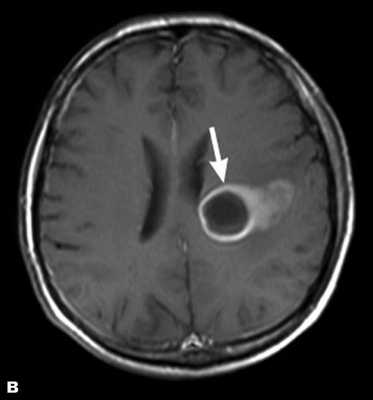

Как выглядит опухоль головного мозга на МРТ- фото

Признаки опухоли на МРТ снимках

- наличие зоны измененного МР-сигнала от тканей мозга;

- гиперинтенсивный МР сигнал, гипоинтенсивный МР сигнал, гетерогенно изменений МР сигнал, изоинтенсивный МР сигнал;

- ориентировочные размеры, форма, контуры объемного образования;

- смещение, давление или изменение величины и деформации желудочков;

- аксиальная дислокация;

- блокада ликворных путей с развитом окклюзионной гидроцефалии;

- наличие перифокального отека;

- латеральная дислокация срединных структур или сосудистого сплетения “масс-эффекта”.